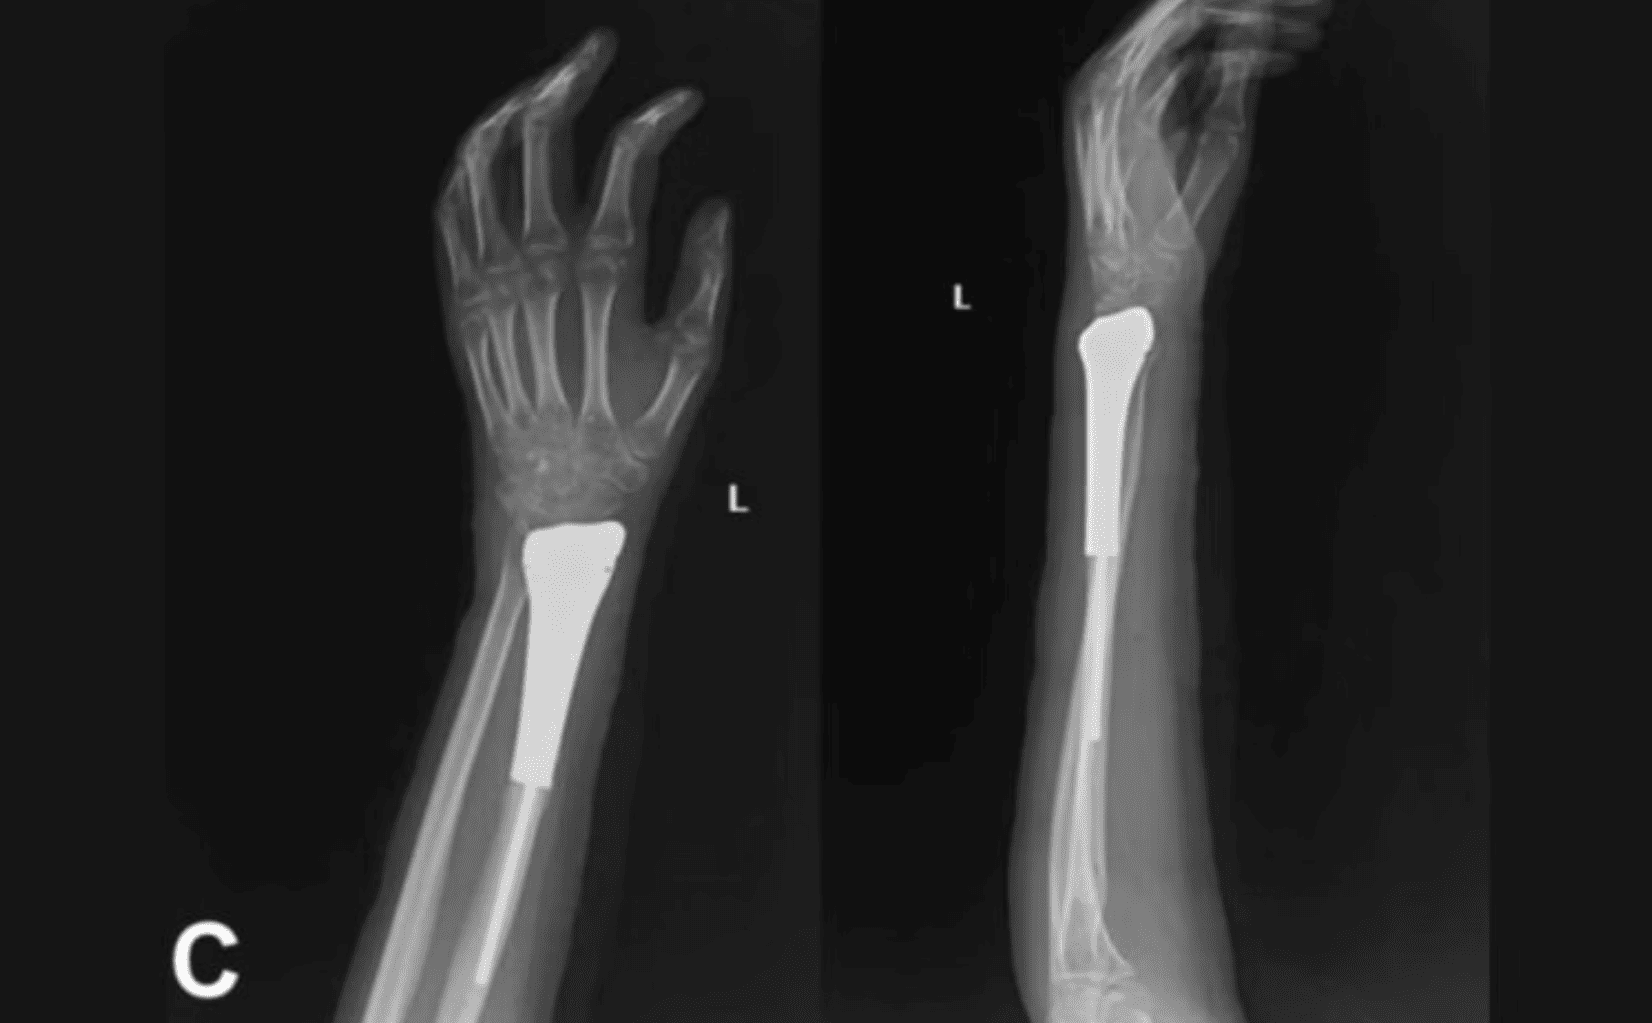

The study team designed fully integrated titanium alloy prostheses from each patient’s CT scans and manufactured the implants with an industry partner. Key design features included a textured stem for improved bone-cement grip, a porous trabecular collar to encourage bone bridging, and prefabricated suture holes on the distal prosthetic surface to reattach ligaments and soft tissue. A two-layer PTFE mesh patch was wrapped and sutured to the prosthesis to create a soft-tissue envelope and stabilize the reconstruction, enabling earlier active motion. The authors outline a reproducible intraoperative workflow for prosthesis placement, ligament repair, and cemented stem fixation.

Functional outcomes were assessed over an average follow-up of 40.8 months (range 32–66 months). At the last follow-up, the mean wrist range of motion on the affected side measured roughly 20° extension and 21.6° flexion, with pronation around 71.2° and supination about 50°; mean grip strength on the treated side was 64.2% of the contralateral hand. The average Mayo wrist score reported was 70, indicating fair to good function. Importantly, the cohort experienced no aseptic loosening, prosthesis infections, or radiocarpal subluxation. There were two cases of distal radioulnar joint (DRUJ) dislocation, and one patient developed ulnar impaction changes by 12 months. No tumor recurrences or metastases were observed during the follow-up window.